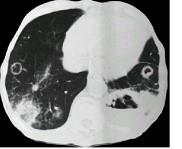

问题 女,52岁,曾患有鼻窦炎,最近发现咳嗽发热,影像学检查如图,最可能的诊断为 ( )

选项 A.多发性肺脓肿 B.浸润型肺结核并空洞形成 C.韦格肉芽肿 D.结节病 E.肺转移瘤

答案 C